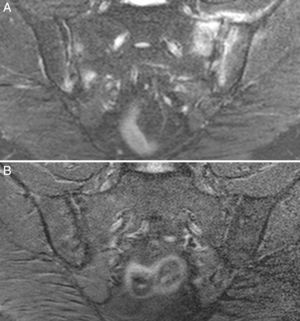

Case no. 2: a 28-year-old woman with a 1-year history of chronic low back pain with inflammatory characteristics and generalized pain that met the criteria for FM. She tested negative for HLA-B27 and positive for antinuclear antibodies (ANA), with a low titer of 1/80, which showed no specificity. Plain radiography revealed sclerosis of both sacroiliac joints, with a difficult differential diagnosis between condensing osteitis and sacroiliitis. On MRI, sclerosis, erosions and bone marrow edema were observed, demonstrating sacroiliitis (Fig. 2). Thus, the patient met the Assessment of SpondyloArthritis International Society (ASAS) criteria for axial spondyloarthritis. Moreover, she had gastrointestinal symptoms associated with dyspepsia, nausea and vomiting. Serological screening for CD was negative. HLA typing revealed the presence of DQ7 and DQ6 and absence of DQ2 and DQ8. The duodenal biopsy revealed intraepithelial lymphocytosis with 44 CD3+ lymphocytes per 100 enterocytes, without villous atrophy. After 7 months of a GFD, there was remission of both low back pain and generalized pain, as well as the gastrointestinal symptoms. After 20 months of follow-up, clinical remission was maintained, and she reported the recurrence of the pain and gastrointestinal symptoms after having ingested gluten.